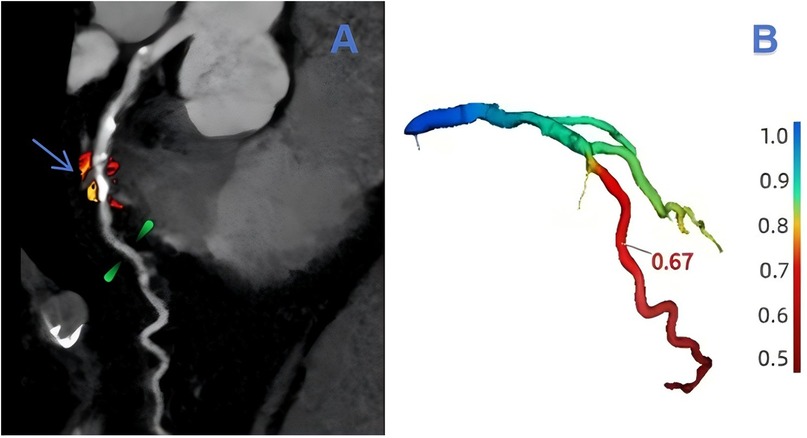

The assessment of lesion-specific peri-coronary adipose tissue in patients with MACE was determined by target plaques, which were identified by CT-derived fractional flow reserve (CT-FFR) analysis (CoronaryDoc®-FFR, Shukun Technology, Beijing, China). A target plaque was defined as a lesion exhibiting a positive CT-FFR < 0.8, measured 2 cm distal to a plaque, indicating a potential impact on the hemodynamics of the corresponding coronary artery (as illustrated in Figure 2). When multiple target plaques existed, the plaque corresponding to the lowest CT-FFR value was selected as the target plaque. Because target plaques may not be present in non-MACE patients in the control group, we chose to perform PCAT segmentation and feature extraction at the narrowest point of the coronary artery in each non-MACE patient. Figure 3 shows the main processes of radiomics.

Figure 2

An example of target plaque selection in the left anterior descending branch (LAD, left anterior decending branch). In (A), the blue-arrowed portion is the area of severe stenosis in the LAD, the green-marked portion is 2 cm from the area of severe stenosis, and the red and orange areas are the outlined extent of lesion-specific peri-coronary adipose tissue. The value of CT-FFR at 2 cm from the region of severe stenosis can be obtained in (B) as 0.67.